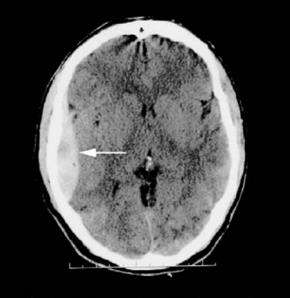

Os hematomas peridurais, conforme observado na imagem, são relativamente incomuns, presentes apenas em 1% dos casos de traumatismo cranioencefálico (TCE), e apenas 10% apresentam rebaixamento do nível de consciência. Quanto aos hematomas peridurais, assinale a alternativa correta.